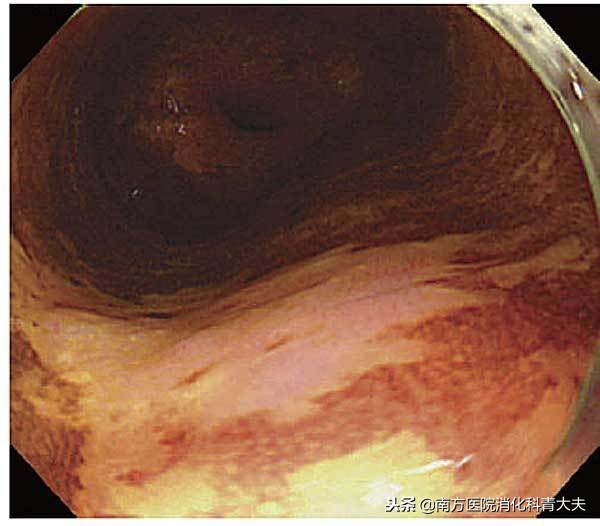

1、"粉色征"

喷洒碘溶液后病变部位呈不染或者淡黄色,2~3 min后,HGIN和癌变部位可变为粉红色。